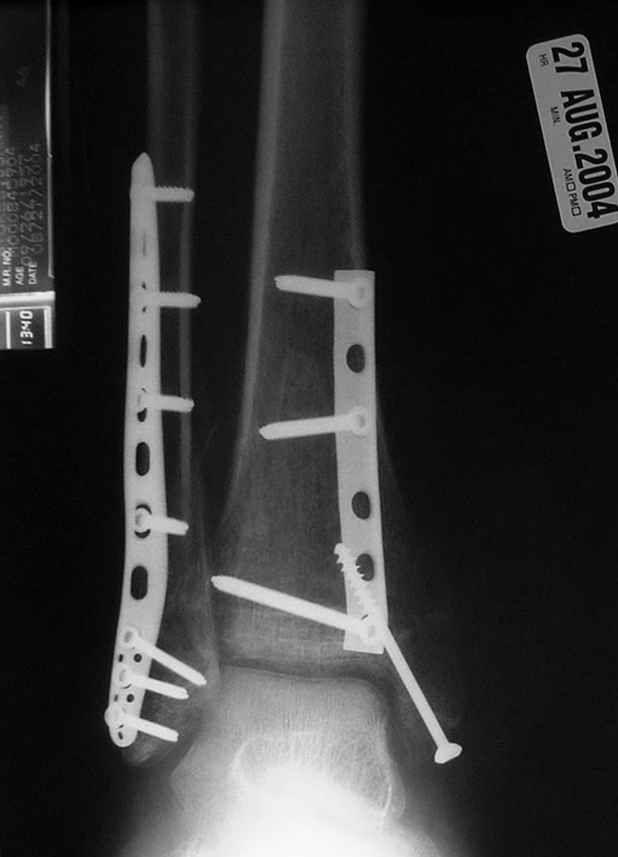

Второй случай сделан из одного разреза

Дж

ЕЧ LISS plate, mininvasive approach - luxurous !

Вопрос практического характера - такой подход рутинный или при определенных показаниях и каких? Спрашиваю потому, что при потоке больных - закрытая голень, бедро, голеностоп и т.д. лучевая нагрузка должна быть немалая, каковы показатели дозиметра после такого операционного дня и при 2-3 операционных днях в неделю по 5-6 случаев (не считая ургентностей)?

С точки зрения : Сгорая сам - свети другим :-)) это вполне понятно, но личная практика показывает, что далеко не все пациенты относятся волнительно и критично к длине кожного разреза. Подозреваю, что это и есть критерий при выборе техники фиксации?

На прямой проекции послеоперационного Рг макроскопически все выглядит очень анатомично, при микроскопическом ( :-)) ) рассмотрении можно все-таки заметить вальгизацию тарана, суставная щель в латеральном отделе сустава несколько уже , чем в медиальном при отсутствии латерального смещения тарана. У меня был аналогичный случай (без LISS , без мини доступа) с вальгусным наклоном тарана при восстановленном ankle mortise при последовательном наблюдении с интервалами в 6-8 недель в послеоперационном периоде отмечалось прогрессирующее сужение суставной щели в латеральном отделе сустава, закончившееся посттравматическим ОА, к счастью боли умеренные, купируемые аналгетиками или своими эндорфинами:-))(активная пациентка, у которой нет времени на болезни....) Какова жизненная ситуация в приведенном вами случае? И последнее, что я хотел бы прояснить для себя - фиксация внутренней лодыжки: я обычно комбинирую фиксацию компрессирующим винтом со спицей - по идее ротационная стабильность должна быть лучше, чем один винт, каковы ваши наблюдения в этом плане?